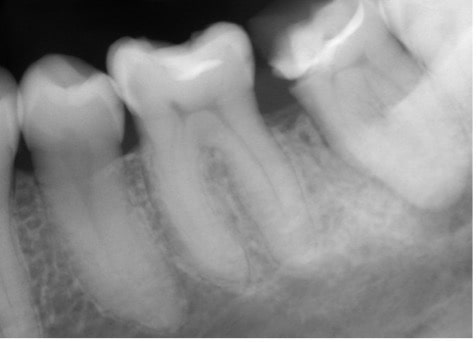

Root Canal Cases by Dr Dana Vosooghi